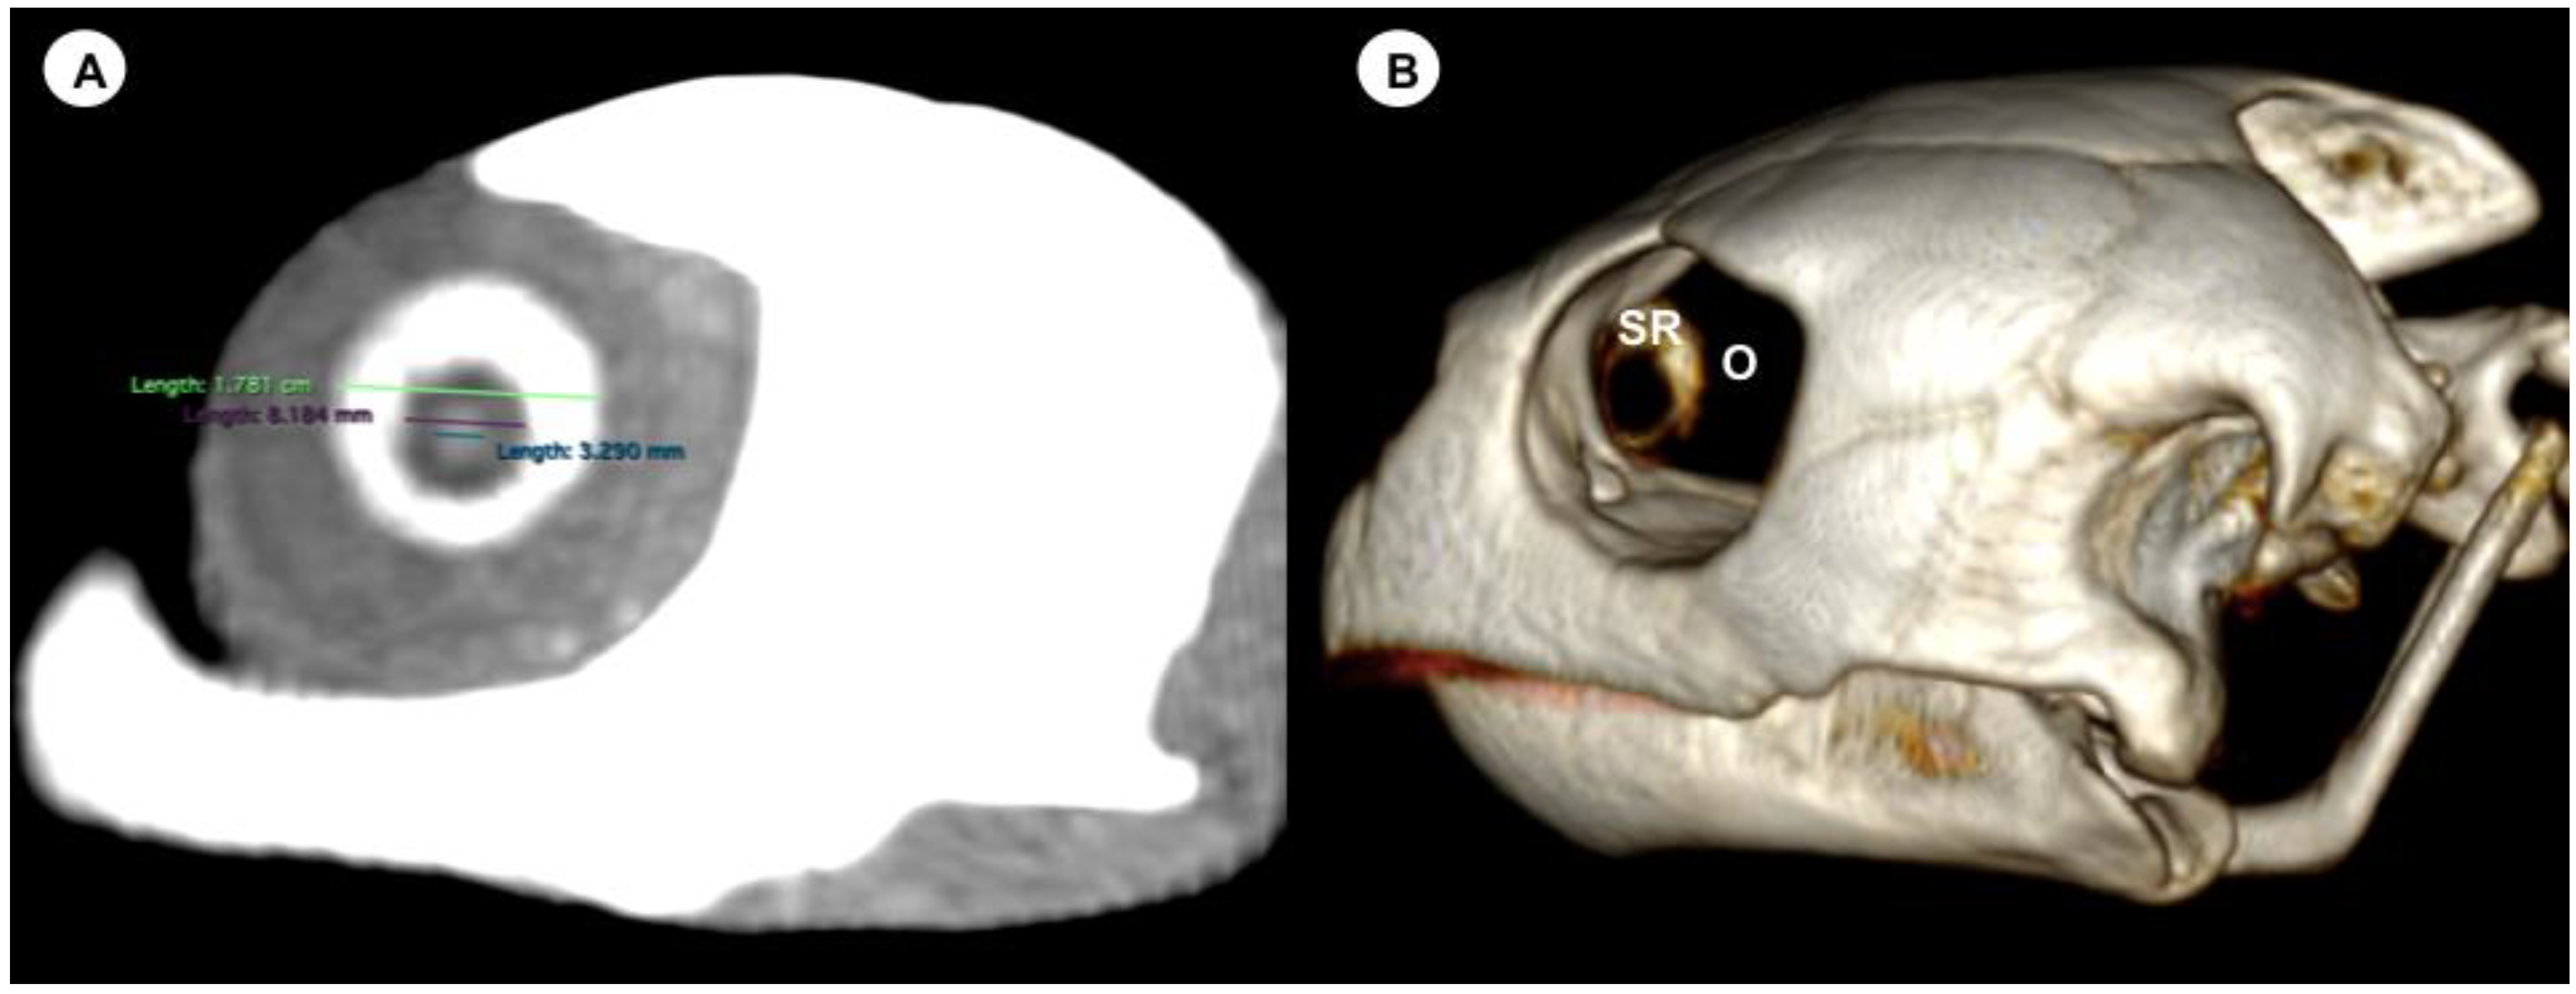

- Lens diameter, understood as the maximum distance between the lateral and medial edges of the lens (equatorial diameter) (Figure 1A).

Figure 1. (A) Transverse multiplanar reconstruction (MPR) related to the eyeball of the C. caretta with measurements of the lens and the internal and external diameters of the sclerotic ring. (B) Volume rendering image of the C. caretta skull with the sclerotic ring (SR) and orbit (O). - -

- Internal diameter of the sclerotic ring, or maximum distance between the inner lateromedial edges of the ring, close to the cornea (Figure 1A).

- External diameter of the sclerotic ring or maximum distance between the outer lateromedial edges of the ring, close to the sclera (Figure 1A).

On the CT image, the eyeball appeared nearly spherical, with a soft tissue attenuating rim in all loggerhead turtles, differing in its sagittal, transverse, and vertical diameters. This border probably represents part of the sclera. Other eyeball structures that were distinguishable were the lens, aqueous and vitreous chambers, and the sclerotic rings (Figure 1). This last chamber was identified as a fluid-attenuating region that accounted subjectively for most of the eyeball volume. In addition, the lens appeared as a spherical hyperattenuated structure suspended in the eyeball and contacting with the vitreous body. The scleral ring, embedded in the rostral portion of the ocular sclera, showed a circular, continuous, and hyperattenuated appearance.

The mean lens diameter was 4.33 mm for all eyes (range = 2.6–5.6 mm). The mean internal diameter of the sclerotic ring was 10.32 mm (range = 6.9–14.7), while the mean external diameter of the sclerotic ring was 16.96 mm (range = 13–22).